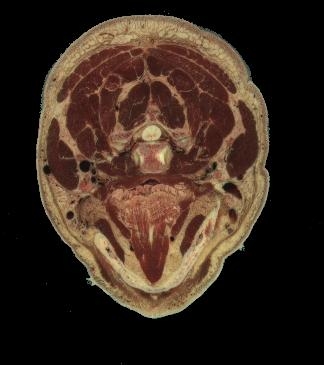

El edema cerebral agudo también provoca una desviación caudal de las estructuras de la línea media con su atrapamiento en la incisura de la tienda o en el agujero magno. Las desviaciones caudales producen la herniación de las circunvoluciones parahipocampales, cerebelo o ambos.

Estos cambios intracraneales aparecen desde un punto de vista clínico como una alteración de la conciencia y de los reflejos posturales. El desplazamiento caudal del tronco cerebral da lugar a parálisis del tercer y sexto pares craneales. Sin tratamiento, estos cambios provocan decorticación o descerebración y pueden progresar rápidamente hasta un paro cardiorrespiratorio.

Los cambios inflamatorios y la destrucción tisular en forma de empiema y abscesos son más pronunciados en la meningitis por gramnegativos. El exudado inflamatorio produce la obstrucción del acueducto de Silvio y otras vías del LCR, lo que origina una hidrocefalia tanto obstructiva como comunicante.